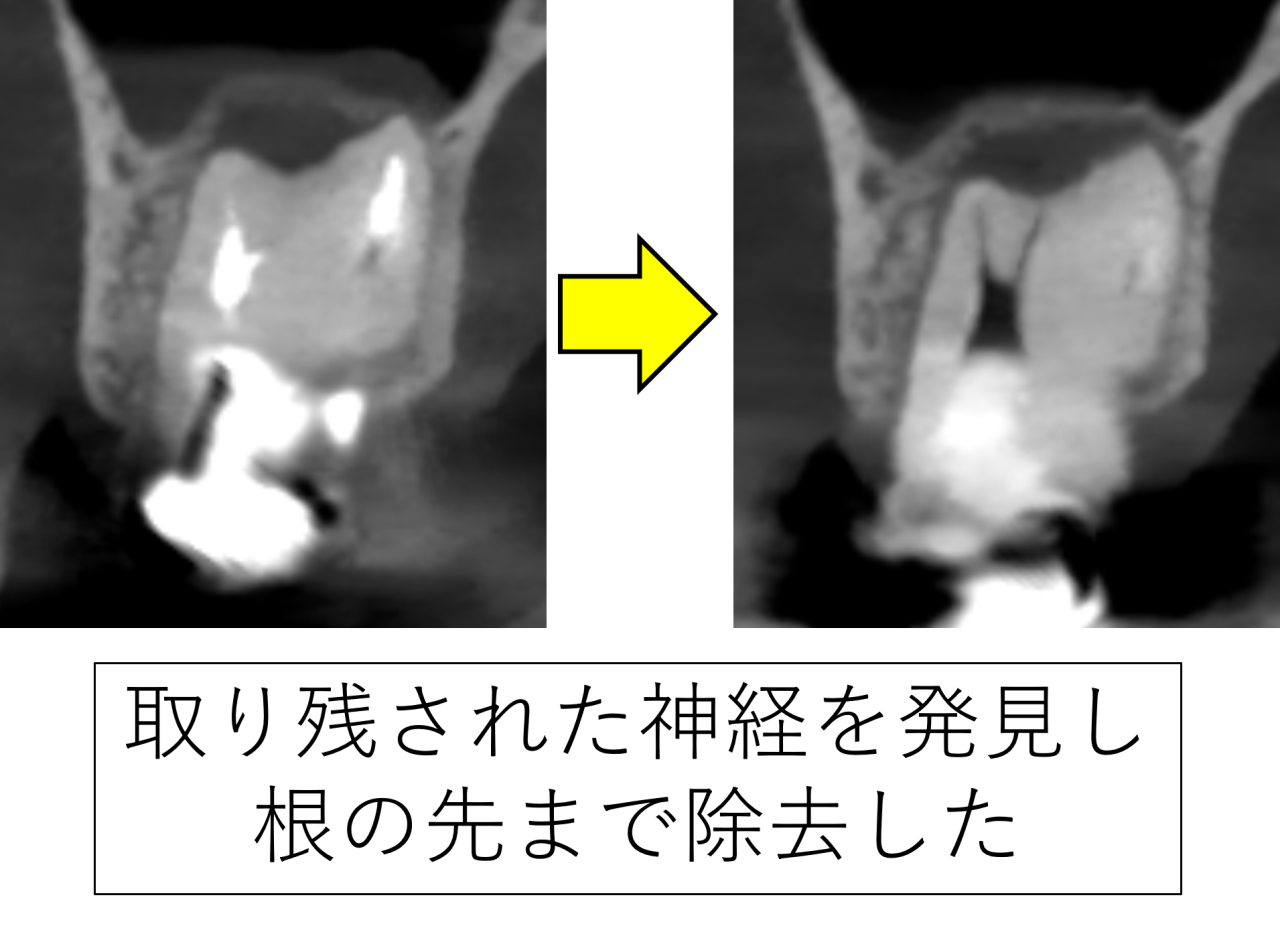

みつおデンタルクリニックでは、再根管治療を行いました。まず、以前に入っていた材料を慎重に取り除きました。古い材料には感染源の細菌があるため、この工程は重要です。

その後、枝分かれした神経の通り道を確認し、感染の原因となっている組織を一つずつ除去しました。複雑な形態では、時間をかけて慎重に進める必要があります。見えている部分だけでなく、見えにくい分岐部まで確認することが大切です。

内部を十分に清掃した後、根の中を封鎖しました。本症例ではMTAセメントを使用しました。MTAは根の先を閉じる目的で用いられる材料の一つで、症例に応じて選択します。